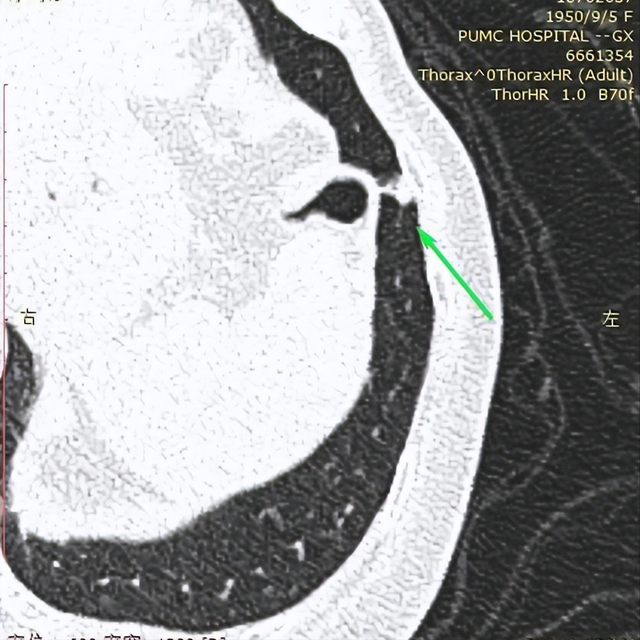

磨玻璃结节很特殊,双肺多发磨玻璃结节更特殊。磨玻璃结节发展有着明确的“路线”,大致为磨玻璃结节→不典型腺瘤样增生→肺原位癌→微浸润性肺腺癌→浸润性肺腺癌。而多发磨玻璃结节,一定程度上可以看作多个“独立”的磨玻璃结节“各自”发展。

所以双肺多发结节虽然听起来很吓人,但选择合适时机一网打尽,那治愈率和单发是一样的。所以多发结节治疗过程中要做到“稳准狠”,“稳”方能寻找时机,治病治心;“准”方能最优手术,保护未来;“狠”方能一网打尽,不留后患。不能抓大放小,因为有可能抓的是原位,放掉的却是浸润;单次单侧的“一网打尽”处理,处理好一边后进行一段时间的休养,待身体恢复,再处理另一侧。

回到今天咨询的这位结友,大半年前在新桥一网打尽右肺高危结节,待身体恢复好了再酌情处理左侧(毕竟73岁高龄,所以在处理的过程中需要特别注意,遵循个体化,精准化)。去年11月在当地随访的过程中,出现新发的结节;加上左肺结节没有处理,于是网络咨询具体下一步方案,看该如何将现有肺结节一网打尽。

这位大姐,您放心,你右肺的剩余和这些新发的结节都是安全的,良性结节。你左肺的结节目前还处于安全状态,原位腺癌接近微浸润腺癌状态,不需要着急手术,按年度安心随访吧,3-5年内都是安全的,只要不明显长大不用管。

左肺结节,还安全,原位后期接近微,3-5年内安全,安心随访,一年一次,不明显长大不管,可控。